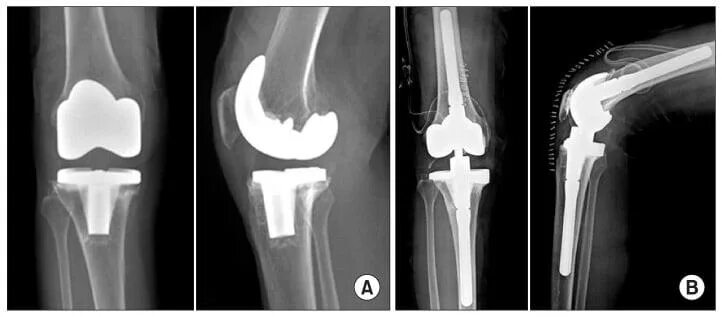

Эндопротезирование коленного сустава время операции